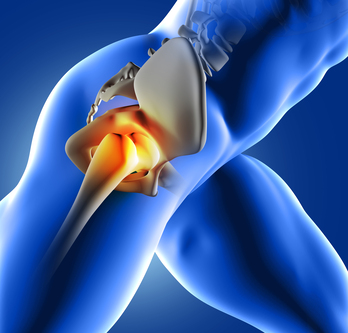

Hip Replacement Surgeon in Pune – Trusted Orthoped...

pune today painfree living improved mobility active lifestyle joint degeneration arthritis fractures patients suffering effective solution crucial step climbing stairs walking standing severely impact alleviates pain chronic hip pain life dont wait minimally invasive procedures hip replacement surgeon